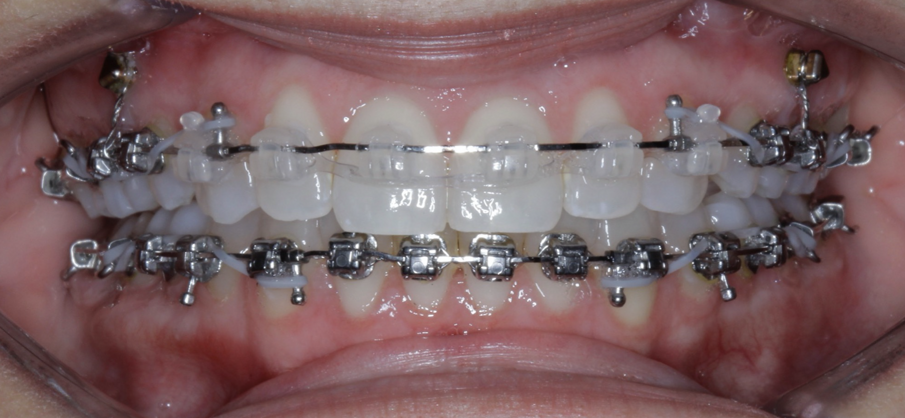

Case 5: Skeletal expansion

In cases where absolute maxillary expansion is desired with little to no dental side effects, maxillary anchorage with TADs is a wonderful solution. This allows for sutural expansion that has little to no dental compensation. Many designs exist for TAD placement with expansion. In some cases, a tissue-borne expander is used with no anchorage on the molars. This is typically used to encourage the maximum amount of skeletal expansion when dental tipping is undesired (Figs. 52 & 53). In cases where molar anchorage is desired, a banded approach can be used in conjunction with TADs (Figs. 54–59).

Fig. 52

Fig. 53

Fig. 54

Fig. 55

Fig. 56

Fig. 57

Fig. 58

Fig. 59